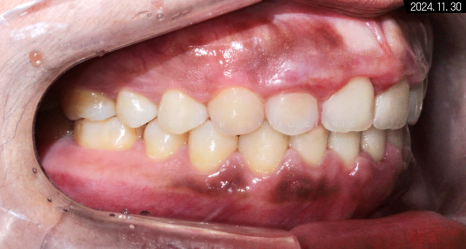

세팔로 사진을 봤을 때에도

눈에 바로 띌 정도로

수평피개가 좋아졌고

윗입술의 도톰함도 해소된 게 보였습니다.

그리고 아래턱이 후하방으로 빠져 있던 것도

돌출입 교정을 통해

전상방으로 비율 좋게 돌아왔습니다.

아직도 살짝 에스테틱 라인에 걸쳐 있지만,

외국인이라는 것을 감안하고 보면

자연스러운 정도의 전돌 양상입니다.

치아 교정 후에 확실히 구강 구조가 가지런해졌으며

각도, 전돌 등 정상 범주를 벗어난 부분까지

바르게 만들어져서 훨씬 보기 좋은 모습입니다.